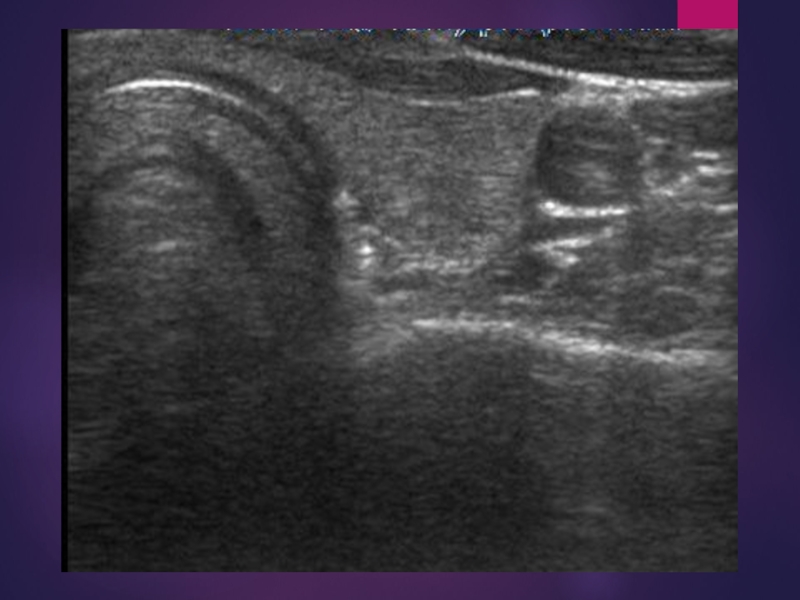

Слайд 14УЗИ сосудов

исследуются магистральные и внутриорганные сосуды: их размеры, расположение, состояние

просвета.

УЗИ сосудов исследуются магистральные и внутриорганные сосуды: их размеры, расположение, состояние просвета.